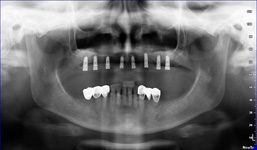

Pro následné plánování využíváme počítačové programy NewTom Implant Planning a coDiagnostiX, které slouží na plánování vhodných pozic pro zavedení implantátů, operačních šablon, kostních bloků, pozdějších protetických náhrad, ...

Plánování v implantologii musí být vždy zaměřeno na optimální výsledek, probíhá tedy obráceně „od konce do začátku“ ošetření – „backwards planning“. Znamená to, že po kompletním vyšetření pacienta, včetně CBCT scanu, zhotovíme pacientovi „model náhrady“ – tzv. Wax up, Set up,

Mock up, tedy jak by mělo definitivní ošetření vypadat. Na základě tohoto modelu pak pomocí plánovacích programů a všech získaných dat naplánujeme počet potřebných implantátů, jejich pozice, délky a průměry.

- operace pomocí OP šablon. Ve speciálním programu coDiagnostiX se využívají data z CB CT scanu - tedy údaje o množství a kvalitě kosti, dále data získaná ze scanu modelu čelistí s modelem plánované protetické náhrady (korunky, můstku…)

- tedy údaje tloušťce sliznice, pozice a tvaru náhrady.

Tím máme všechny potřebné údaje pro plánování pozic implantátů, jejich potřebné délce a průměru. Abychom mohli implantáty zavést do naplánovaných pozic v ústech pacienta, umožňuje tento program vymodelovat speciální operační šablonu, která je zhotovena 3D tiskárnou. Pomocí této šablony, která se umístí do úst pacienta, pak probíhá vlastní operace

- zavádění implantátů.

Jedná se o plánovací program, který využívá dat získaných při vyšetření pomocí přístroje New Tom. Tento program umožňuje tříprostorovou počítačovou simulaci při plánování pozic implantátů.

Součástí programu je i databáze, ve které mohou být uloženy všechny typy implantátů od všech výrobců, včetně jejich délek, průměrů i tvarů.

Lékař si vytvoří všechny typy zobrazení potřebných pro naplánování – tedy 2D snímky (panoramatický), příčné řezy i 3D model.

Vidí zde i důležité anatomické útvary – čelistní dutinu, průběh nervu atd. Po proměření množství kosti – šířky i výšky vybere z databáze vhodný typ implantátu a umístí ho do požadované lokality.

Ihned vidí jeho pozici ve všech 3 rovinách a na všech snímcích i 3D modelu. Může upravovat podle potřeby jeho pozici, sklon atd.

Všechny vybrané a správně umístěné simulované implantáty se ukládají do „počítačové karty“ pacienta s jejich pozicí, délkou, průměrem, typem i sklonem.

Lékař i pacient tedy ještě před vlastní operací vidí, jak by mělo ošetření probíhat a vypadat.

Jedná se o externí plánovací program, spojený se zubní laboratoří a frézovacím centrem, který využívá dat získaných z 3D rentgenu čelisti, otisku zubů a dásně (scanu zubů a dásně) a finálního návrhu protetické náhrady.

Tento program umožňuje tříprostorovou počítačovou simulaci při plánování pozic implantátů. Součástí programu je i databáze, ve které mohou být uloženy všechny typy implantátů od všech výrobců, včetně jejich délek, průměrů i tvarů.

Vidí zde i důležité anatomické útvary – čelistní dutinu, průběh nervu atd. Po proměření množství kosti – šířky i výšky vybere z databáze vhodný typ implantátu a umístí ho do požadované lokality. Ihned vidí jeho pozici ve všech 3 rovinách a na

všech snímcích i 3D modelu. Může upravovat podle potřeby jeho pozici, sklon atd.

Všechny vybrané a správně umístěné simulované implantáty se ukládají do „počítačové karty“ pacienta s jejich pozicí, délkou, průměrem, typem i sklonem. V programu také lékař navrhuje chirurgické šablony pro řízenou nebo navigovanou implantaci.